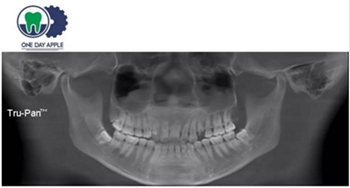

正畸支抗直立47

第一次支抗釘脫落, 第二次支抗釘位于48位置, 頰側(cè)舌側(cè)舌側(cè)扣牽引。

直立后維持位置, 并取模戴牙。